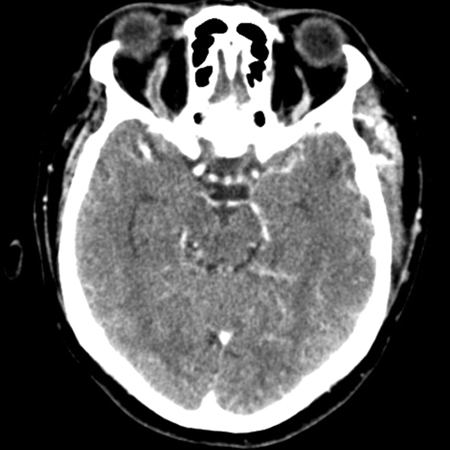

Tomografia computadorizada (TC) de crânio na fase pós-contraste venosa (visão axial) revelando uma veia oftálmica superior direita aumentada em forma de "S" associada a proptose

Jones RG, Arnold B. Sudden onset proptosis secondary to cavernous sinus thrombosis from underlying mandibular dental infection. BMJ Case Rep. 2009;2009. pii: bcr03.2009.1671. Usado com permissão